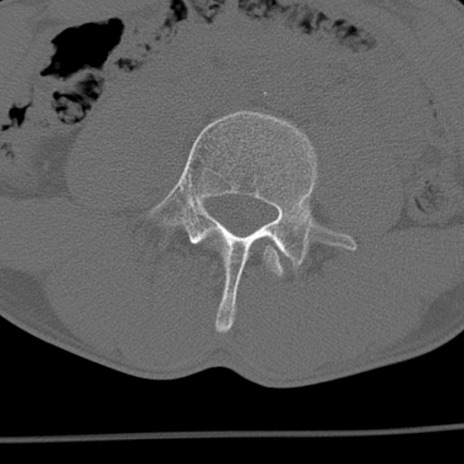

症例3 腰椎CT(横断像)

腰椎CT